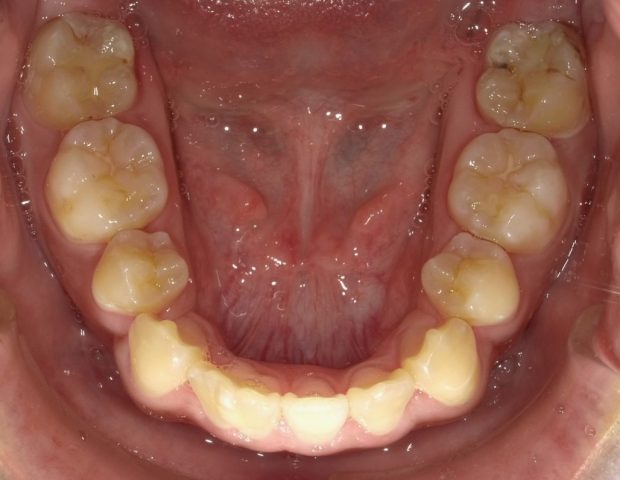

【下顎咬合面観】

2023年1月